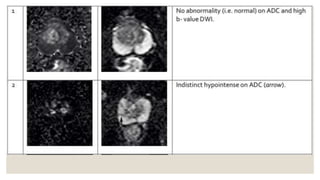

◦ Diffusion weighted imaging (DWI)

◦ 1: no abnormality and ADC and high b-value DWI

◦ 2: indistinct hypointense on ADC

◦ 3: focal mildly/moderately hypointense on ADC and isointense/mildly hyperintense on high b-value DWI

◦ 4: focal markedly hypointense on ADC hyperintense on high b-value DWI; <1.5 cm in greatest

dimension

◦ 5: same as 4 but ≥1.5 cm in greatest dimension or definite extraprostatic extension/invasive behavior